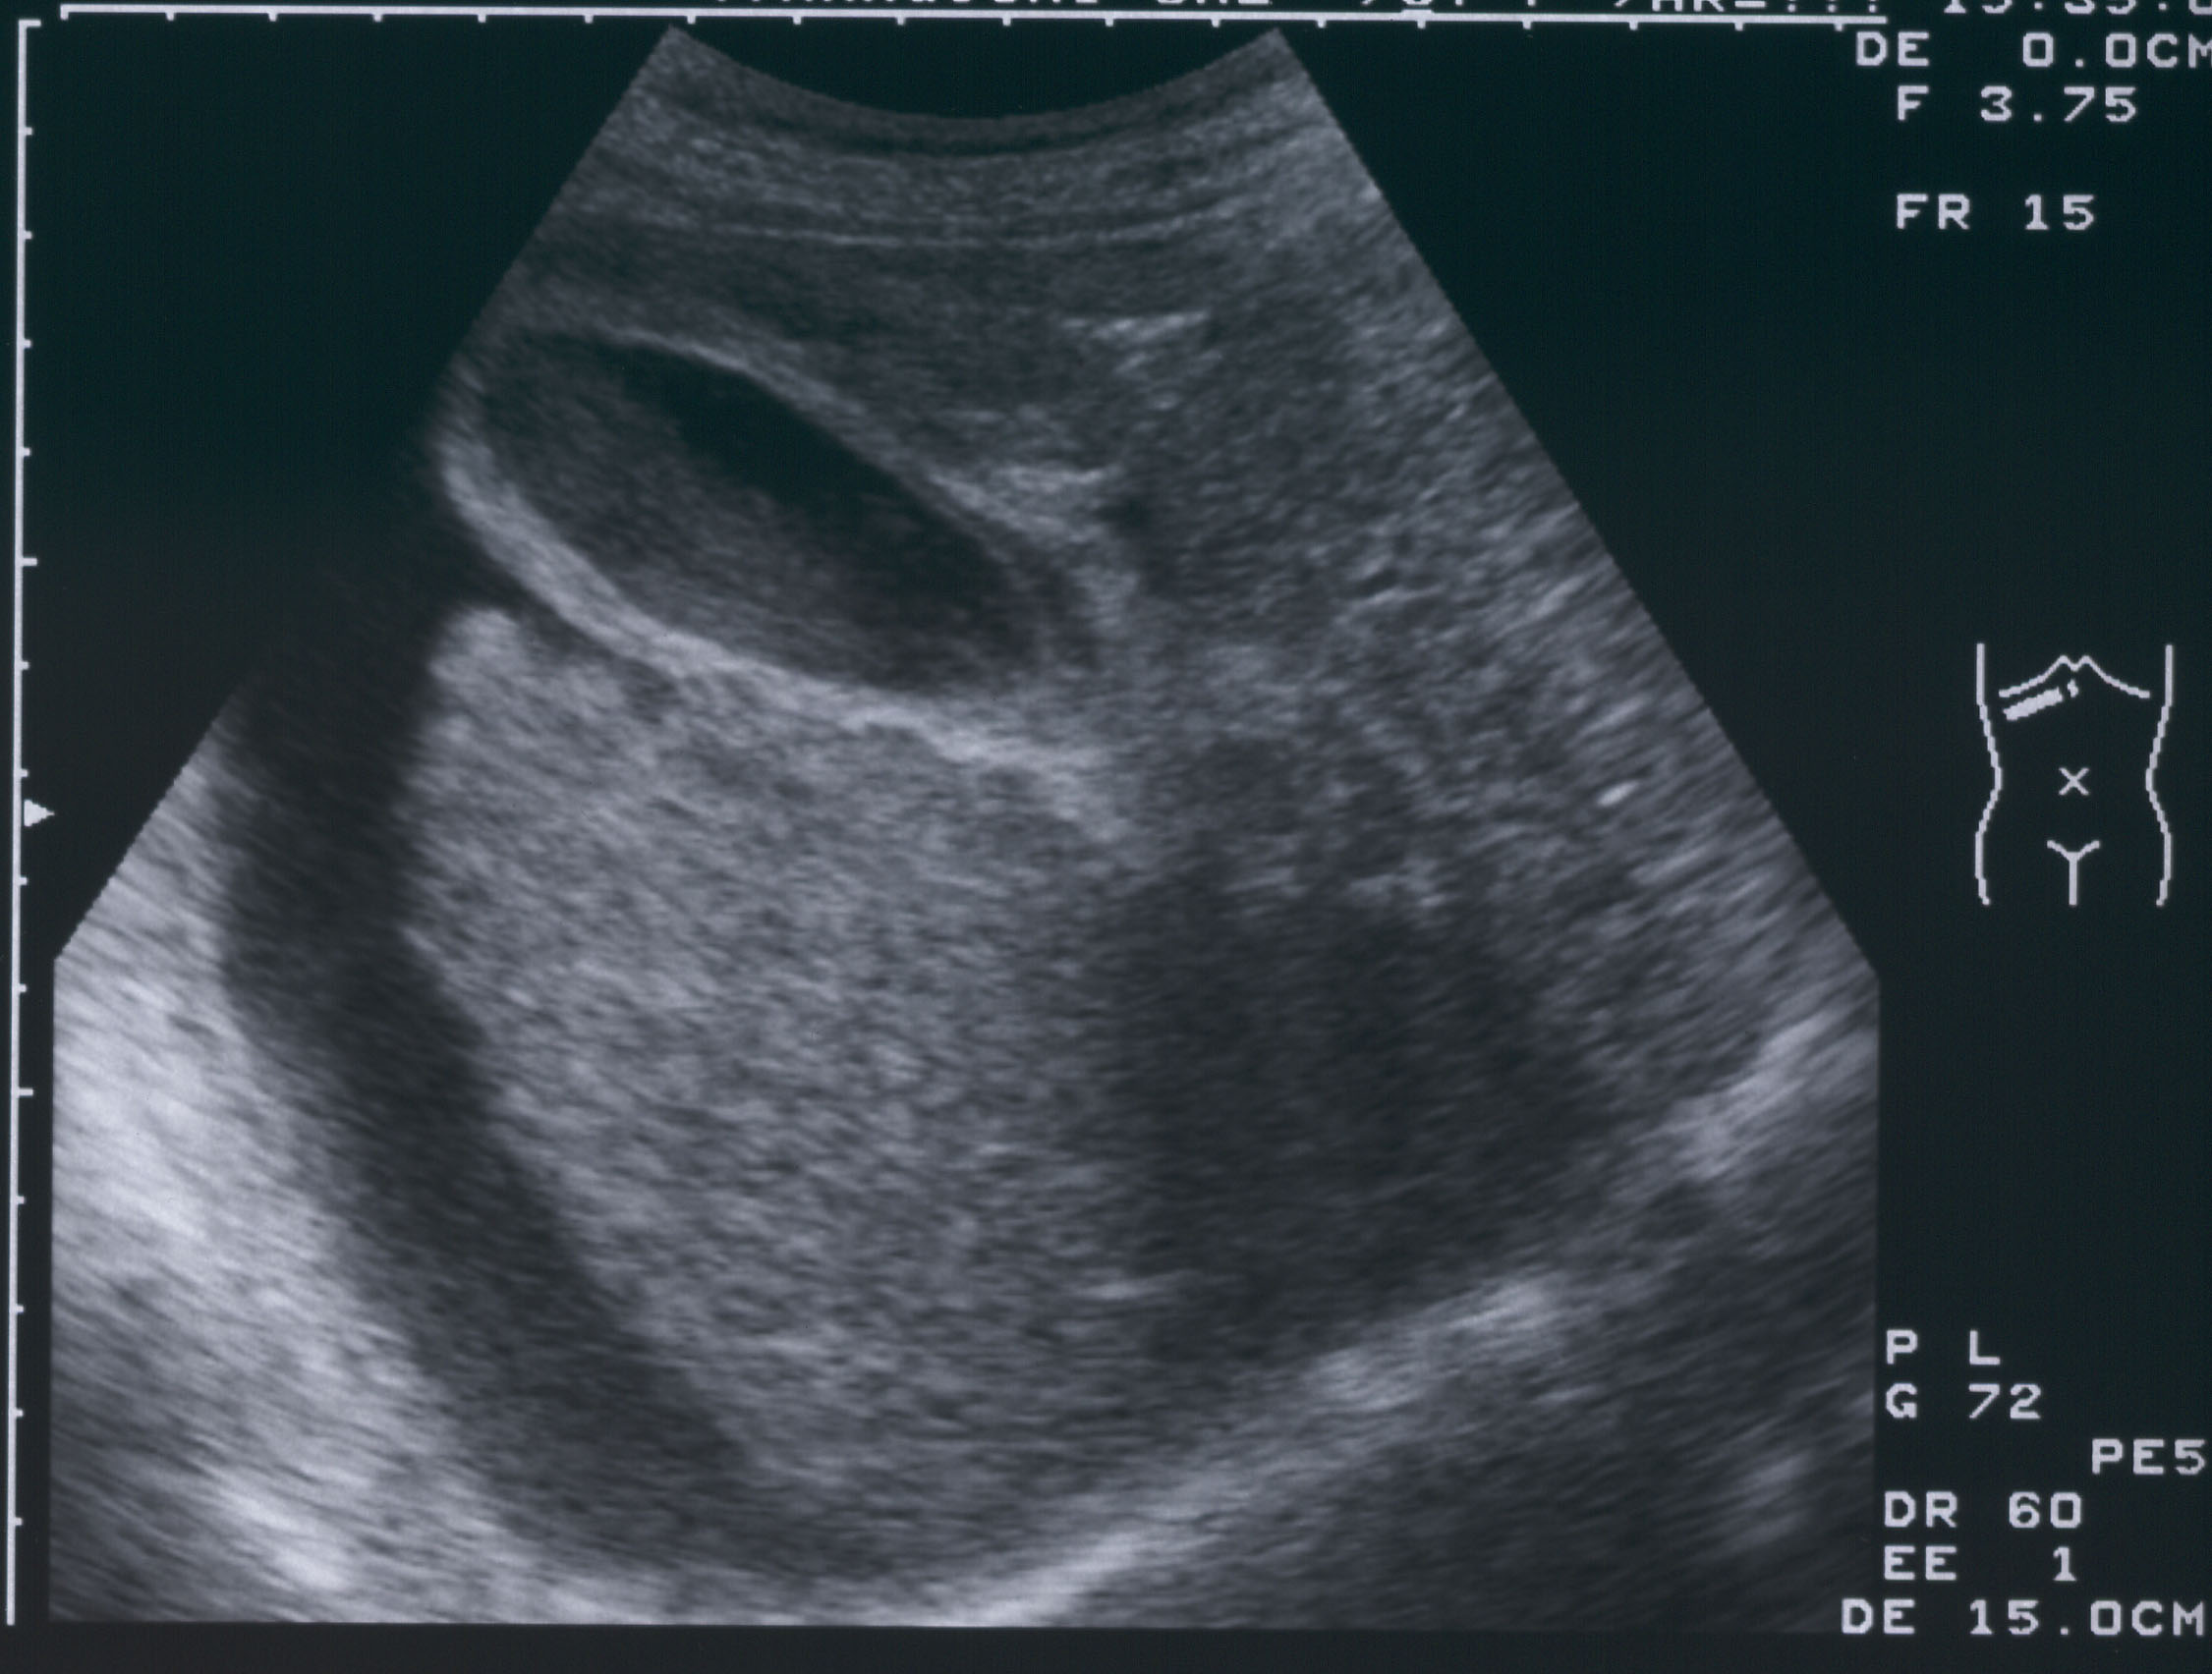

肝硬変の診断方法

検査により、肝臓がどの程度損傷しているかを明らかにすることができます。肝硬変の評価に使用される検査には次のようなものがあります。

肝臓を評価できる追加の検査には次のものがあります。